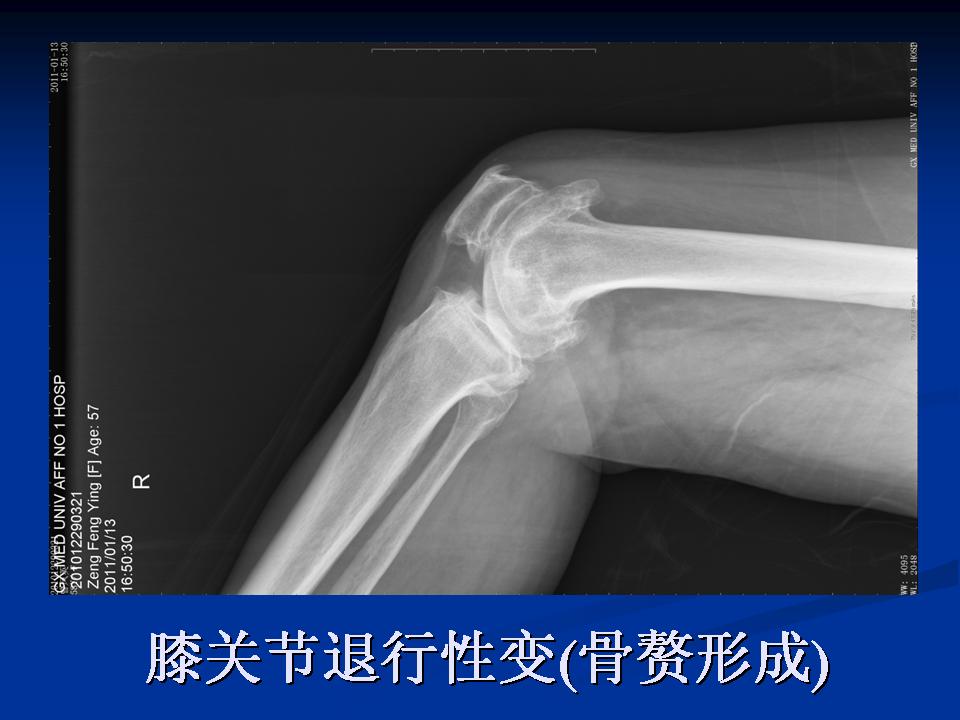

影像学检查 X线 四个方向X线影像 l 早期可无改变 l关节间隙变窄、不均匀、消失(成人<3mm; 老年人<2mm)。 l骨赘形成 l关节内游离体、骨质疏松 l软骨下骨板硬化、囊性变

膝关节退行性变 ( 骨赘形成 )